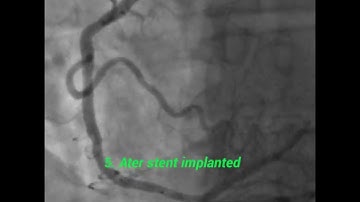

In-Stent Occlusion True Lumen Crossing with TruePath